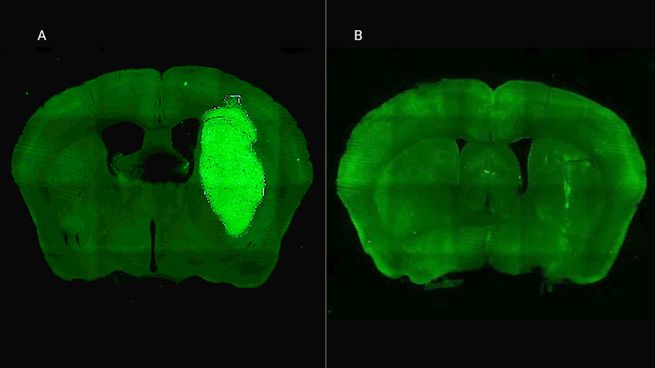

Además de aumentar la sensibilidad del tumor a los tratamientos convencionales, P60 redujo la viabilidad y migración de las células cancerígenas e inhibió la proliferación de células endoteliales, esenciales para la progresión del glioblastoma. Los estudios se realizaron en modelos celulares murinos y humanos, incluyendo cultivos derivados de biopsias de pacientes del Instituto FLENI, que reflejan la heterogeneidad del tumor.